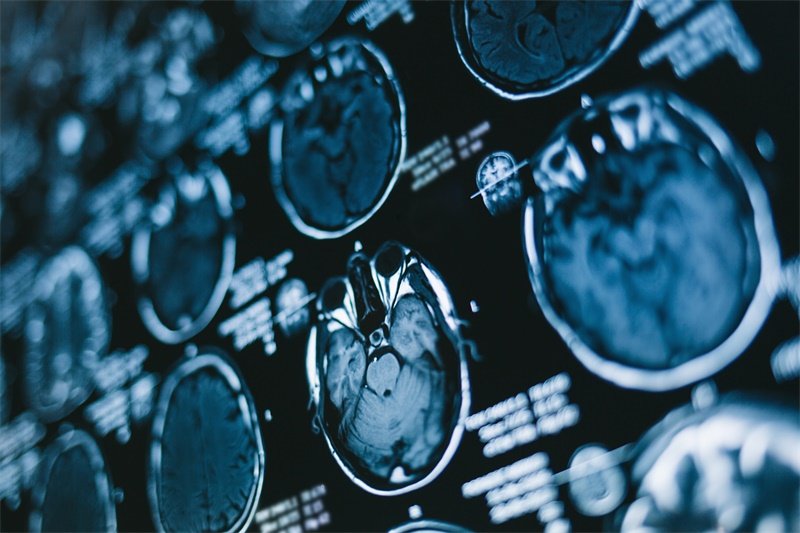

影像学检查

影像学检查是诊断视神经占位的主要方法,常用的有磁共振成像(MRI)和计算机断层扫描(CT)。MRI能够提供视神经及其周围结构的详细信息,有助于判断肿瘤的性质和大小。

视神经占位的确诊通常通过影像学检查如磁共振成像(MRI)和计算机断层扫描(CT)来完成。有时需要进行病理学检查以获得更详细的病变信息。